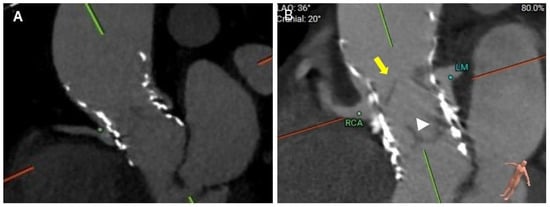

4.4. Coronary Risk Plane (CRP)

4.5. Leaflet Overhang

5.1. Coronary Occlusion Risk During Redo-TAVR and the Need for Protection